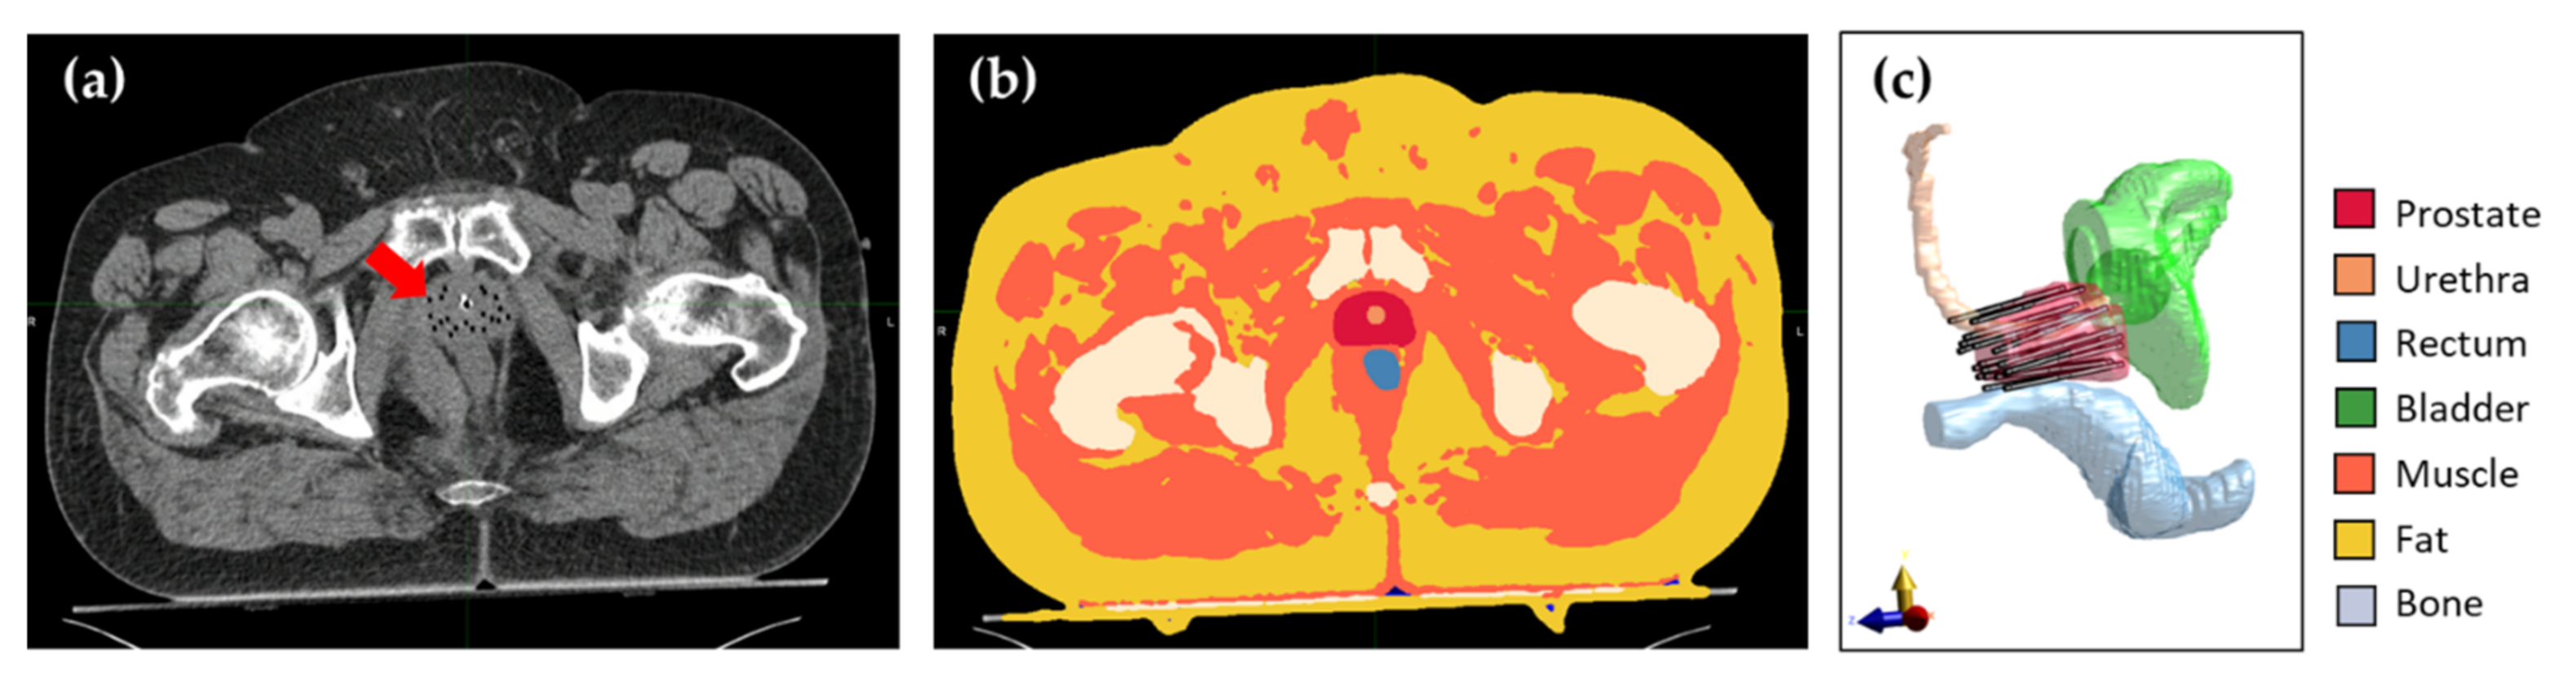

2.2. Patient Anatomy Modeling